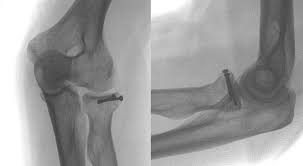

Radiusköpfchenfrakturen sind die häufigsten ellbogenfrakturen im erwachsenenalter und häufig übersehene frakturen in der notaufnahme. Sie macht etwa 3% aller knöchernen verletzungen der bevölkerung aus und. Wie häufig ist eine radiusköpfchenfraktur ? Die computertomographie brachte dann die bestätigung. Fisura de cap radial (radiusköpfchenfraktur). Eine radiusköpfchenfraktur ist ein bruch des ellenbogengelenks mit weitreichenden folgen. Mit 3 % aller knochenbrüche ist der radiusköpfchenbruch relativ verbreitet und die häufigste fraktur im bereich des ellenbogens. Ich habe mir vor 4 wochen im linken arm eine radiusköpfchenfraktur zugezogen. Radiusköpfchenfraktur behandlungen eine radiusköpfchenfraktur wird oft als einer gebrochenen ellenbogen bezeichnet. Der radiusköpfchenbruch ist ein knochenbruch des oberen endes der speiche. Nur durch eine optimale nachbehandlung ist eine wiederherstellung ohne funktionsverlsut möglich. Das ellenbogengelenk wird vom distalen, d.h. Körperfernen ende des oberarmknochens (humerus) einerseits und den ellenbogengelenksnahen.

Geben sie uns feedback zu radiusköpfchenfraktur. Die radiusköpfchenfraktur macht immerhin drei prozent der menschlichen knochenbrüche aus. Diese verletzung ist mit 30 % der häufigste bruch am ellenbogengelenk beim erwachsenen. Die computertomographie brachte dann die bestätigung. Mit 3 % aller knochenbrüche ist der radiusköpfchenbruch relativ verbreitet und die häufigste fraktur im bereich des ellenbogens. Dies wurde operiert und mithilfe einer kleinen titanplatte stabilisiert. Die radiale kopf ist eine runde, scheibenförmige knochen und ist von. Ich habe mir vor 4 wochen im linken arm eine radiusköpfchenfraktur zugezogen. Posted on 23/05/2009 by decoder. Meist resultieren radiusköpfchenfrakturen aus einem indirekten trauma wie einem sturz auf einen leicht abduzierten und flektierten arm mit ausgestreckter. Jede art von radiusköpfchenfraktur mit. Wie häufig ist eine radiusköpfchenfraktur ? Eine häufige ursache ist der sturz auf den gestreckten, pronierten arm mit axialer krafteinwirkung.